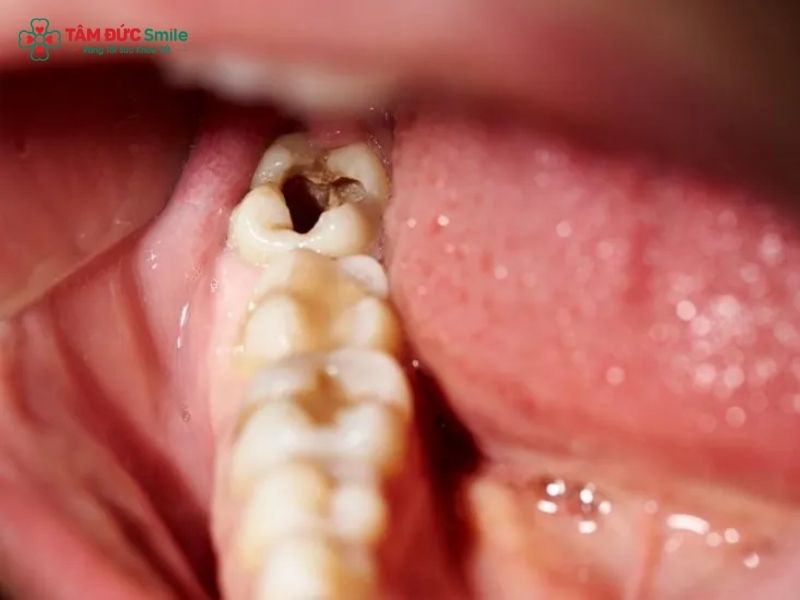

Over time, repeated acid attacks lead to enamel demineralization. Once the enamel is breached, bacteria can penetrate the softer dentin layer, accelerating the decay process. At this stage, cavity symptoms such as sensitivity or discomfort may begin to appear. Without timely cavity treatment, decay can reach the tooth pulp, where nerves and blood vessels are located.

- Visible pits, holes, or dark spots on the teeth